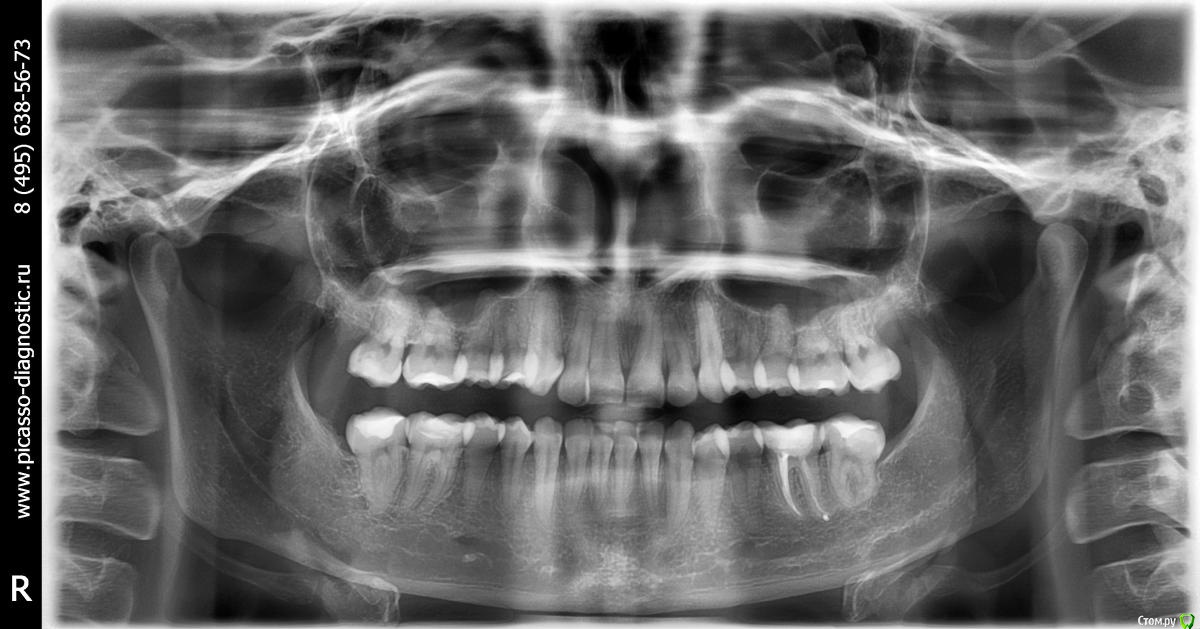

Екатерина556 Опубликовано 16 августа, 2015 Поделиться Опубликовано 16 августа, 2015 Добрый день! Обращаюсь с просьбой о консультации, а также может быть кто-то сможет посоветовать лечащего врача.В детстве носила брекеты, однако после того как их сняла и начали расти 8-ки зубы опять сдвинулись. На текущий момент все восьмерки удалены и хочу понять целесообразность еще раз проходить через брекеты. Лечащий врач сказал, что без удаления зубов в моем случае ничего не получится. Хотела бы понять действительно ли это так? И вообще в моем случае насколько возможно сделать все качественно, чтобы потом ничего никуда не разъехалось. Также большая просьба посоветовать компетентного врача, которым мог бы помочь с данной проблемой.Снимки прилагаюг. Москва Ссылка на комментарий

Екатерина556 Опубликовано 22 августа, 2015 Автор Поделиться Опубликовано 22 августа, 2015 Фотографии Ссылка на комментарий